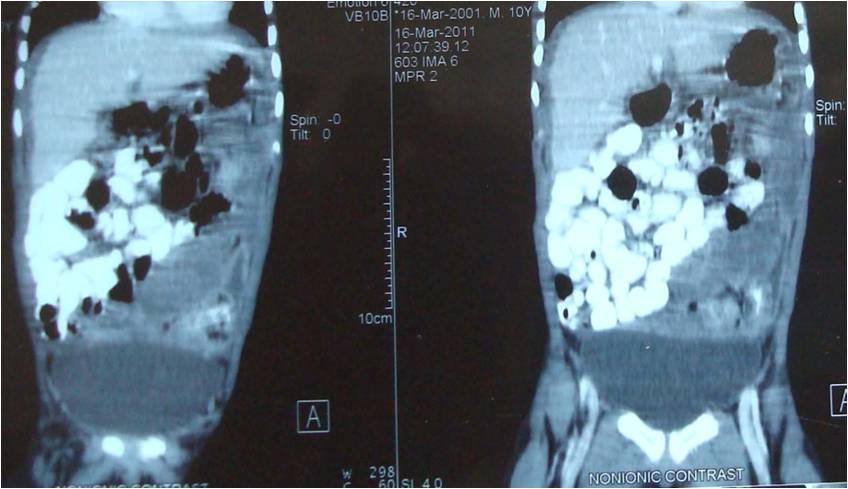

cavity. CT scan showed thick omentum, matted gut

loops with lymphadenopathy and fluid collection in the peritoneal cavity (Fig.

1,2).

Figure 1: Thick omentum, matted gut loops

with ascitic fluid collection.

Figure 2 : Thick solid (cake) omentum pushing all the small bowel loops towards

right lower quadrant with encapsulation of the colon.

In

our patient CT scan showed, thickened omentum almost occupying the whole of

abdomen pushing the matted thick walled gut loops towards one side with ascites.